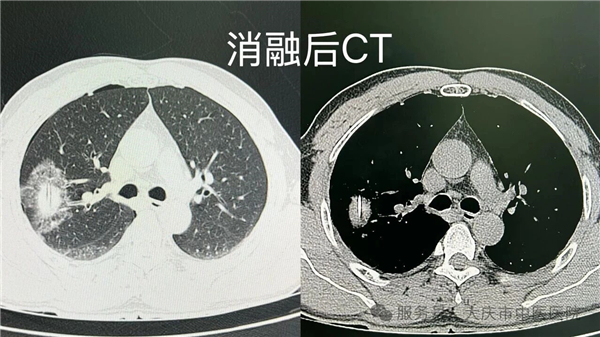

近日,在我院肺结节门诊牵头下,微创介入科联合 CT 室,成功开展一例肺结节同步病理活检与射频消融诊疗术。该技术在局部麻醉下,通过微创方式,同步完成病理活检取样与射频消融治疗,术中患者生命体征平稳,术后恢复良好。

本次开展的同步诊疗技术,在 CT 精准定位下,通过消融针到达病灶区域实施消融治疗,并通过同一通道获取组织标本进行病理检查,实现诊断与治疗环节的紧密衔接,有助于缩短诊疗周期,减少多次操作可能带来的相关风险。该技术的成功开展,是我院多学科协作及学科群建设的一次实践,为肺结节诊疗提供了新的技术选择。

很多患者查出肺结节后陷入两难:随访担心延误,手术又怕身体扛不住。以射频消融为代表的微创介入技术,恰好为肺结节患者提供了另一种选择。

仅针对结节本身,对周围正常肺组织几乎无影响,尤其适合高龄、心肺功能差、多发结节或拒绝外科手术的患者。